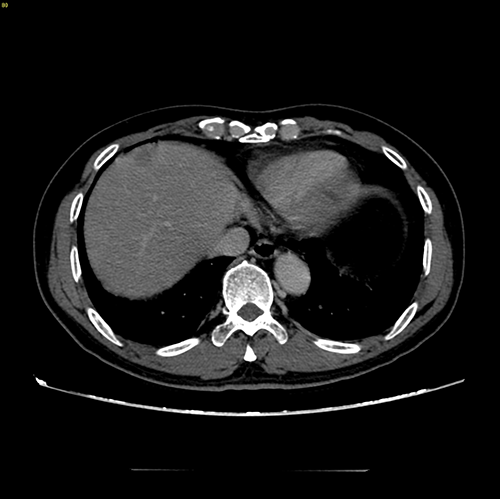

S58 肝癌--腹腔镜S58部分切除